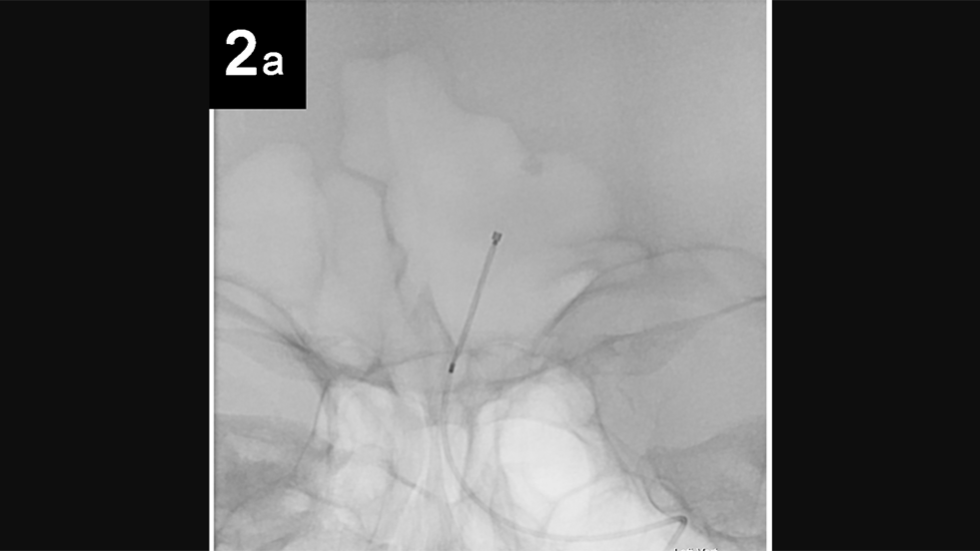

Intrasaccular: 2a

2 of 6